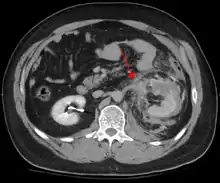

کوبیدگی بطنی، شامل ۷۵٪ از تمامی موارد کوبیدگی و معمولترین نوع از این قبیل آسیبها است.[1] عامل اصلی این نوع آسیب، حوادث وسایل نقلیهٔ موتوری است. در این حوادث، به سبب برخورد شدید راننده با فرمان (خودرو)، داشبورد، یا کمربند ایمنی،[2] بسته به میزان نیروی وارد شده، در موارد خفیف به ضرب دیدگی و در موارد حادتر، به سبب افزایش فشار داخل مجرا، به ترکیدگی اندامهای داخلی بدن میانجامد.